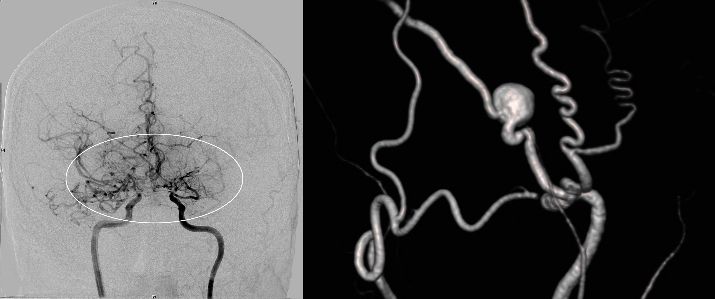

Die konventionelle cerebrale Angiographie ist die wichtigste Untersuchung zur Diagnosestellung der Moyamoya Krankheit. Diese Untersuchung ist zu vergleichen mit einer Herzkatheteruntersuchung, eben nur mit Darstellung der Hirnarterien. Bei Moyamoya-Patientinnen und Patienten werden, im Gegensatz zu Routineuntersuchungen bei anderen cerebralen Erkrankungen, selektiv die vordere und hintere Zirkulation des Gehirns dargestellt, sowie auch die Versorgung der extrakranialen Gefäße. Diese umfassende Darstellung ist besonders wichtig, um die vollständige Ausdehnung der Erkrankung zu erfassen und alle möglicherweise veränderten Blutflüsse im Gehirn zu verstehen. Je nach Befund werden die Engstellen der Hirnarterien, sowie auch mögliche begleitende Veränderungen selektiv hochauflösend dreidimensional dargestellt. Es ist wichtig zu erwähnen, dass die Moyamoya Krankheit nicht über eine Katheterintervention (Ballonaufweitung der Engstelle) behandelt werden kann und darf. Dies haben mehrere Studien gezeigt.

Angiographie beidseitige Moyamoya Krankheit

Konventionelle Angiographie eines Patienten mit beidseitiger Moyamoya Krankheit (links). 3-dimensionale Darstellung eines Aneurysmas einer jahrelang stark beanspruchten Spontan-Kollaterale (rechts).